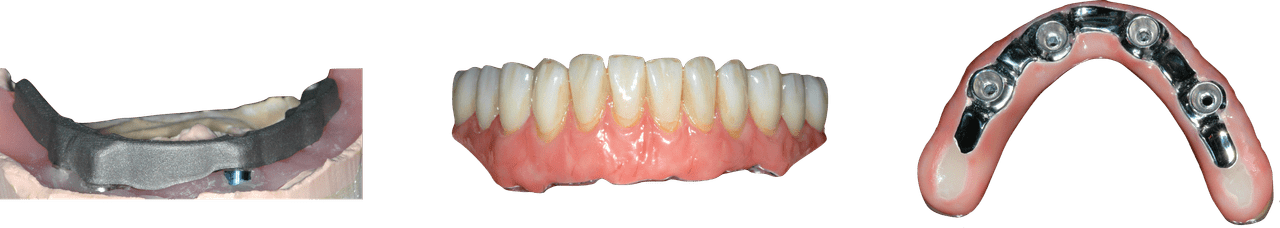

This mastery-level course discusses both the prevention and management of surgical and restorative complications. Within the surgical realm, the presentation focuses on early implant failure and later peri-implant disease. Prosthetic concepts will involve preventative prosthesis design, screw/abutment removal, and sequencing that acknowledges the importance of patient experience.

The implant curriculum is an interactive, procedure-based series of courses that use individual cases to teach current implant treatment. This approach is in contrast to conventional dental education that focuses more on didactic topics and theory. The purpose of using this educational approach is to highlight the patients and procedures found in everyday clinical practice, where the most important concepts are observed and discussed in multiple clinical scenarios.